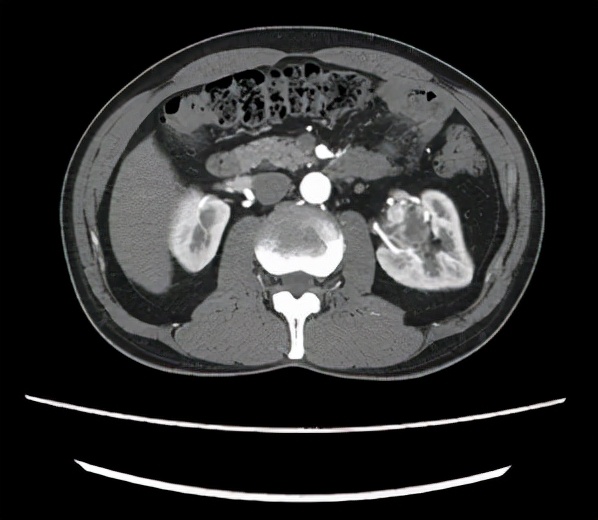

(胡先生的左腎腫瘤)

浙大二院泌尿外科的裘益青主任醫師接診了胡先生。面對胡先生的情況,裘醫生仔細閱片,告訴胡先生他的年齡不大,腎功能尚可,左腎腫瘤形態和密度考慮惡性腫瘤,而且體積較大,位置較深,位於腎門,需行保腎的腫物切除手術,手術難度較大,建議使用達芬奇機器人輔助手術。

術前,裘醫生在科室進行了手術討論,決定了機器人輔助下腹腔鏡經後腹腔的手術方式。手術開始,裘醫生充分遊離左腎周筋膜,開闊視野,暴露腎臟中上極背側腎門部約4.5cm的那枚“定時炸彈”,它突出腎臟表面,盤踞腎門,血管包繞與周圍組織明顯粘連,若要完整剝除必定是一場硬戰。